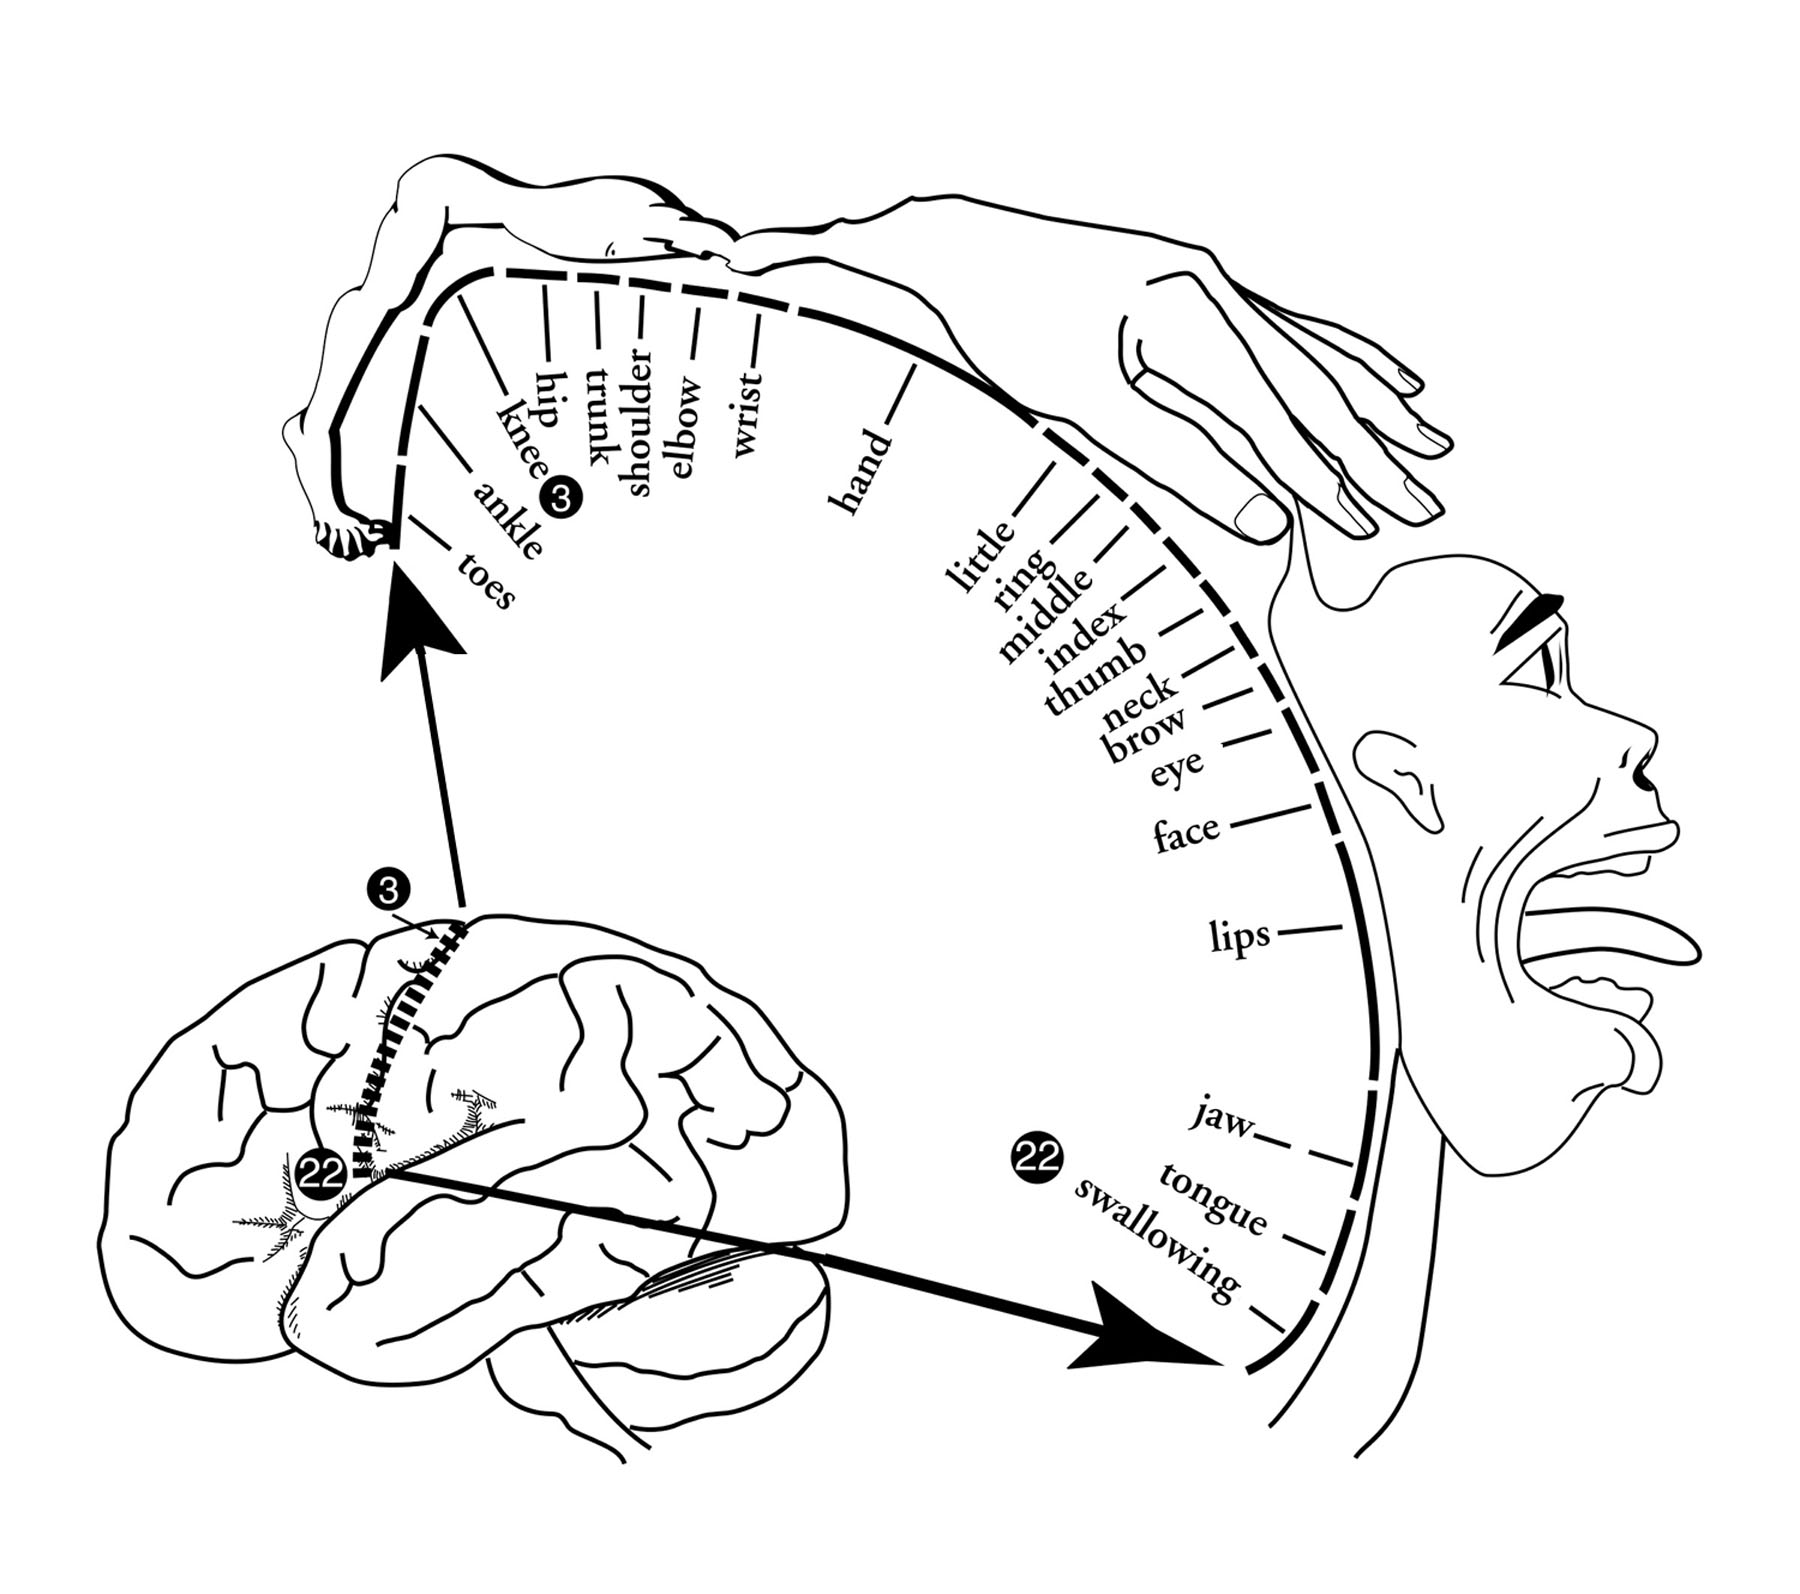

The Homunculus

Scientists can map which parts of the brain control various parts of the body. The mapping is done by stimulating the sensory or motor cortex with a weak electric current. The stimulation often produces tingling or movement in part of the body.

Humans put great emphasis on speech and manipulation of objects by the hands, so humans have large amounts of cortex devoted to mouth, tongue, and hands. Different species have different patterns. Rats get a lot of information from their whiskers, so they have large amounts of sensory cortex devoted to their whiskers.

The following diagram represents a slice of cortex near the fissure of Rolando, running from the top of the head down toward the ear. The diagram indicates the location and amount of cortex devoted to each part of the body.

For example, just above the lateral fissure by the ear, stimulation produces a swallowing reflex. At a location on the top of the head, stimulation results in toe movement.

The map of brain connections to the body, in this particular strip of cortex, is depicted below. The amount of cortical tissue is represented by the size of the body part in the diagram.

How is the homunculus mapped out?

The Homunculus, based on Penfield's classic diagram

The diagram looks a bit like a grotesque little man, so it is called the homunculus (ho-MUN-q-lus) which means "little man" in Latin. The first homunculus diagram was drawn by brain surgeon Wilder Penfield in the 1940s.

Notice that the hands, lips, and tongue are large. That is because the figure is drawn to reflect how much cortex is devoted to each area of the body.

The homunculus is a textbook diagram, certainly is not a self or center of consciousness in the brain. However, humorous references to the homunculus as a little person in the head are common among psychologists.

There are many homunculi in the brain, if the word refers to an area of cortex where body surfaces are mapped. Such maps can change with experience.

People who read Braille (which is done with an index finger) develop large areas responsive to stimulation from the index finger. A homunculus mapped on the motor cortex of such a person would have a huge index finger.